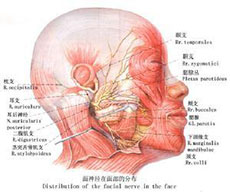

带状疱疹病毒性睑皮炎

疾病介绍:本病是由带状疱疹病毒感染三叉神经半月神经节或三叉神经第一支所致,多见于老年人或体弱者。多有发热、乏力、全身不适的前驱症状。随后病变区出现剧烈…【详细】